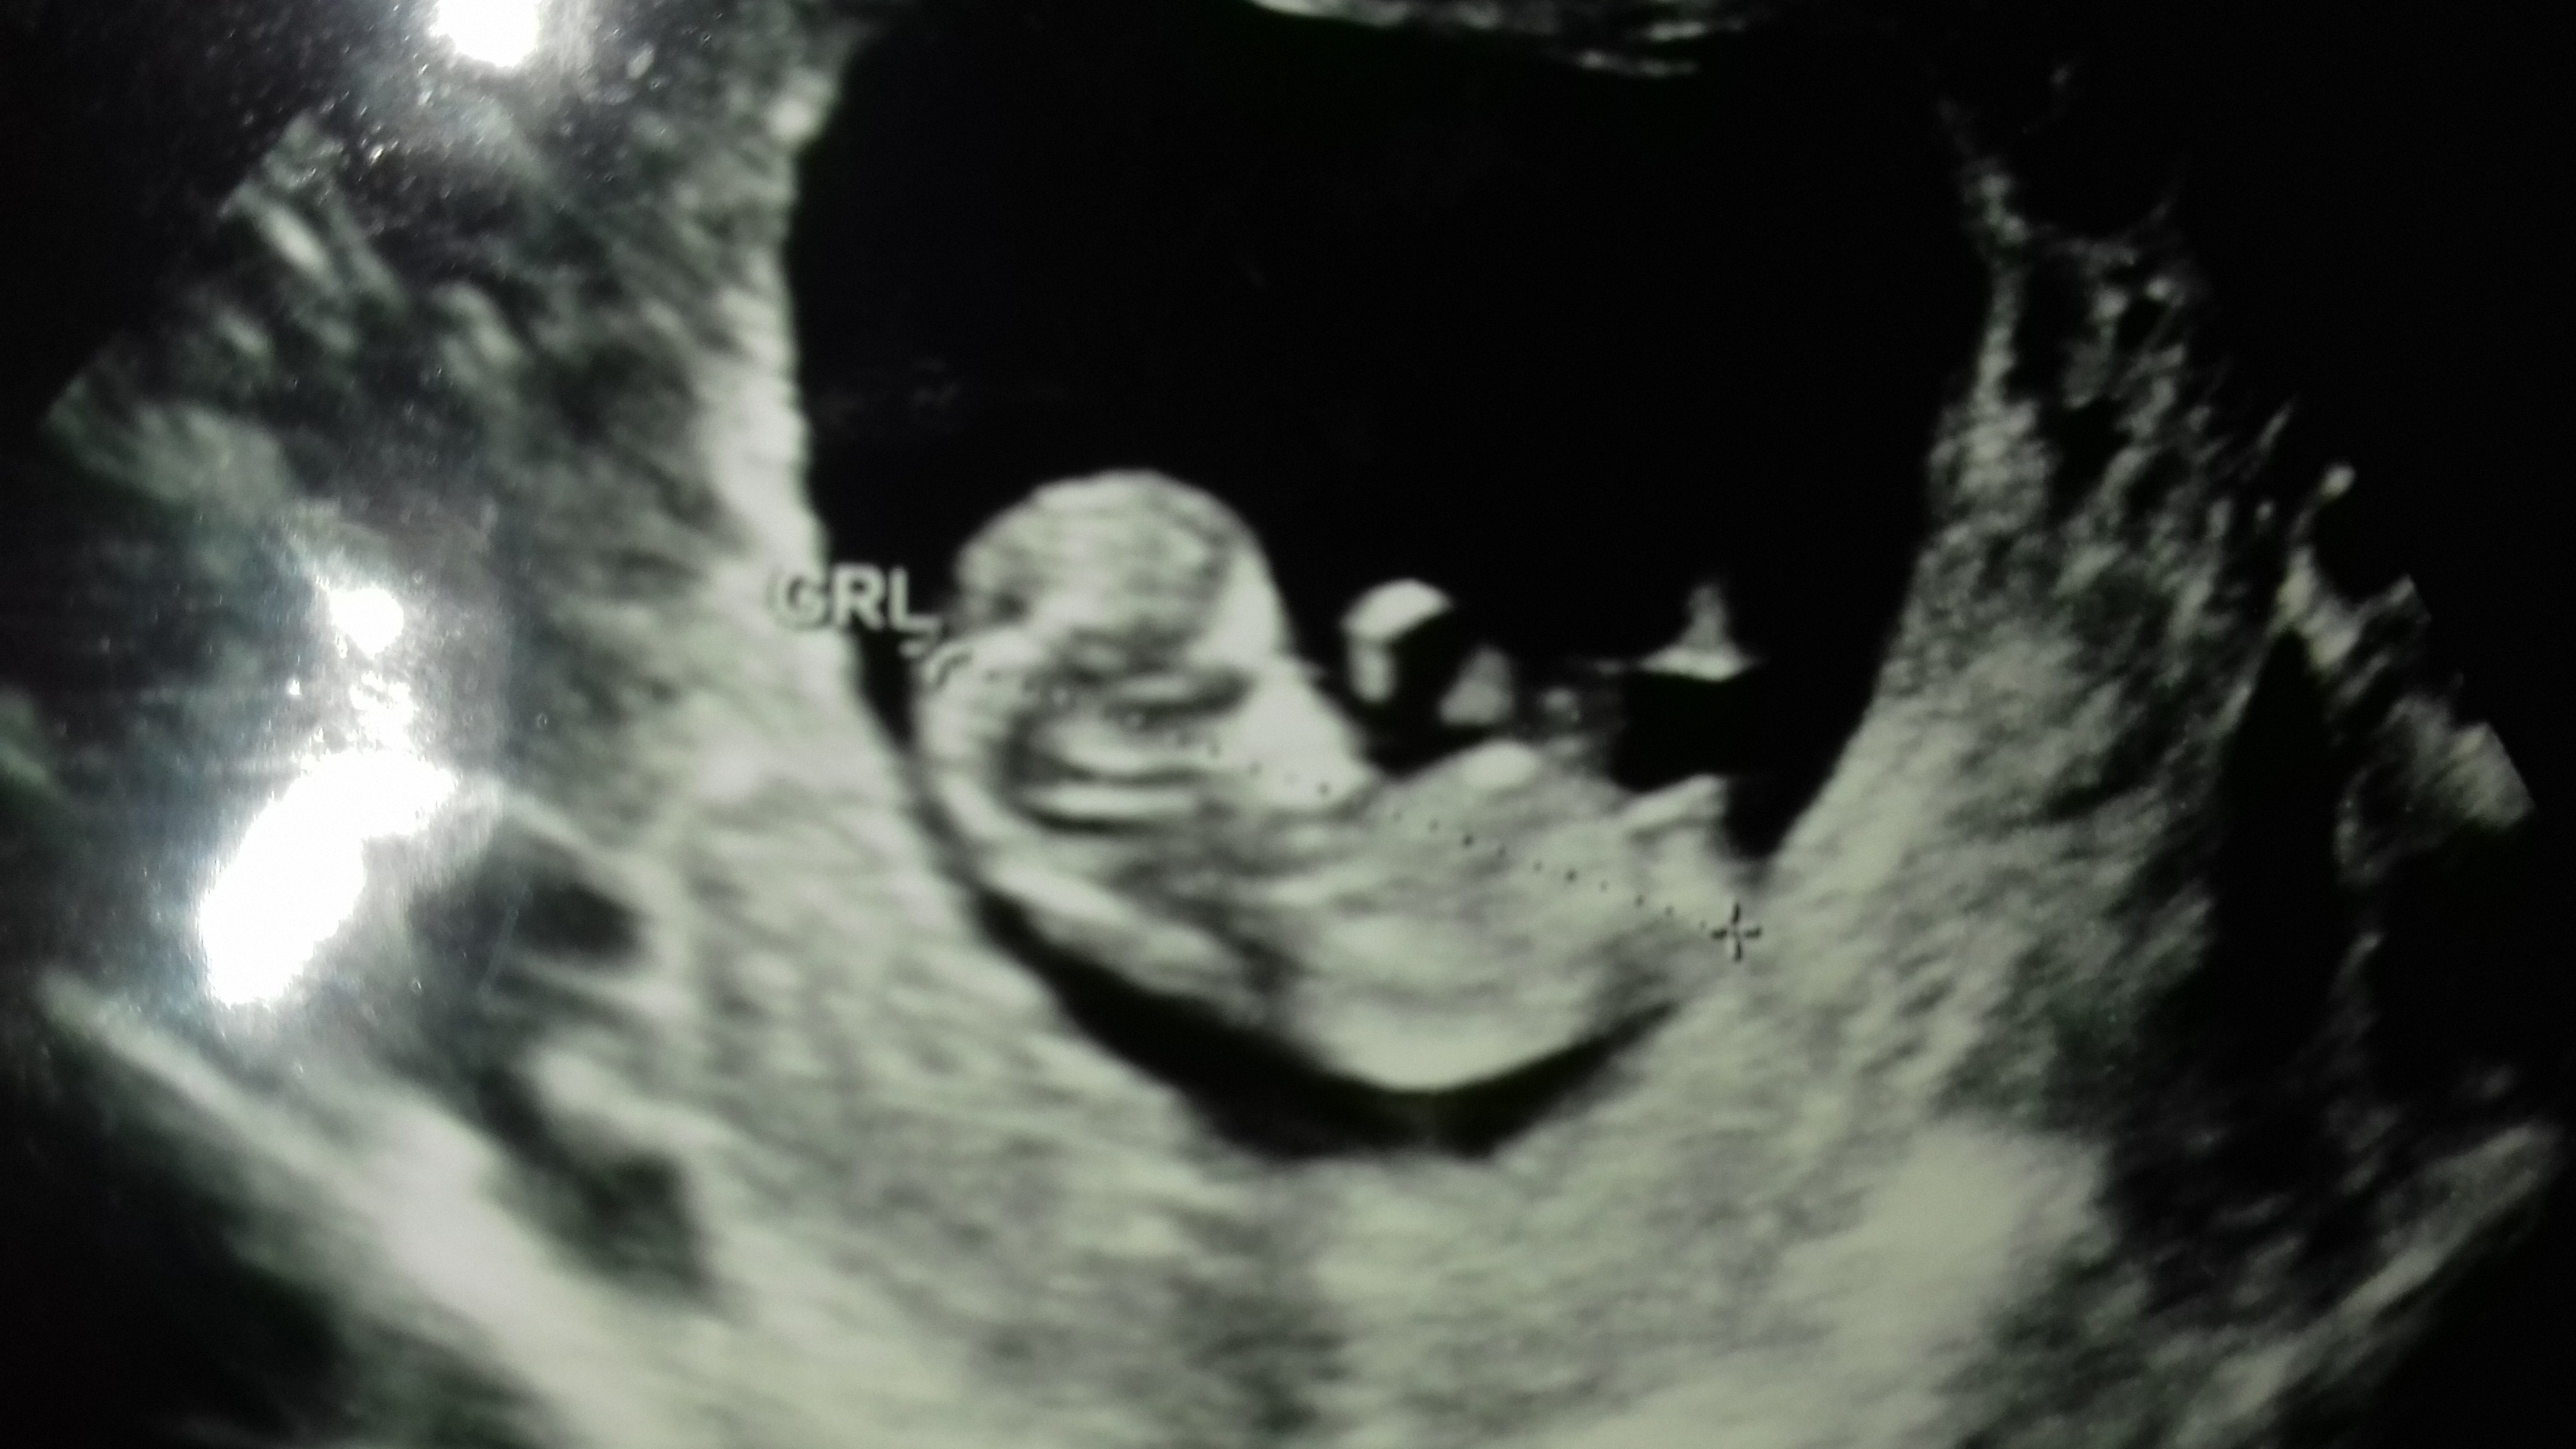

Last pics look more girly but I think boy, hope I'm wrong. First one looks like boy nub and second one would look girly if no stacking (but could very well be baby's leg in the way). Even the last pic has a line under nub which might suggest boy. But really hope it is your baby girl!

I thinking girl. FX for you!

I'm leaning girl. What gestation are the most recent pics from? If they are 13+ weeks, then I would most definitely say girl.

I'm still leaning more towards girl because at this gestation all of my boys had a clearly visible scrotum and penis. While anything is possible, I think that potty shot is swollen girl bits.